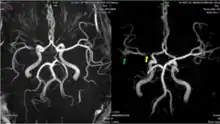

The leptomeningeal collateral circulation (also known as leptomeningeal anastomoses or pial collaterals) is a network of small blood vessels in the brain that connects branches of the middle, anterior and posterior cerebral arteries (MCA, ACA, and PCA),[1] with variation in its precise anatomy between individuals.[2] During a stroke, leptomeningeal collateral vessels allow limited blood flow when other, larger blood vessels provide inadequate blood supply to a part of the brain.[3]

MRI and CT brain imaging is used to determine the severity of a stroke, and help guide treatment. Fluid attenuated inversion recovery (FLAIR) vascular hyperintensity (FVH) is a radiographic marker seen on brain imaging in acute ischaemic stroke. FVH can be used as a proxy for slow leptomeningeal collateral blood flow, and may help reveal which areas of brain tissue are potentially salvageable.[12]